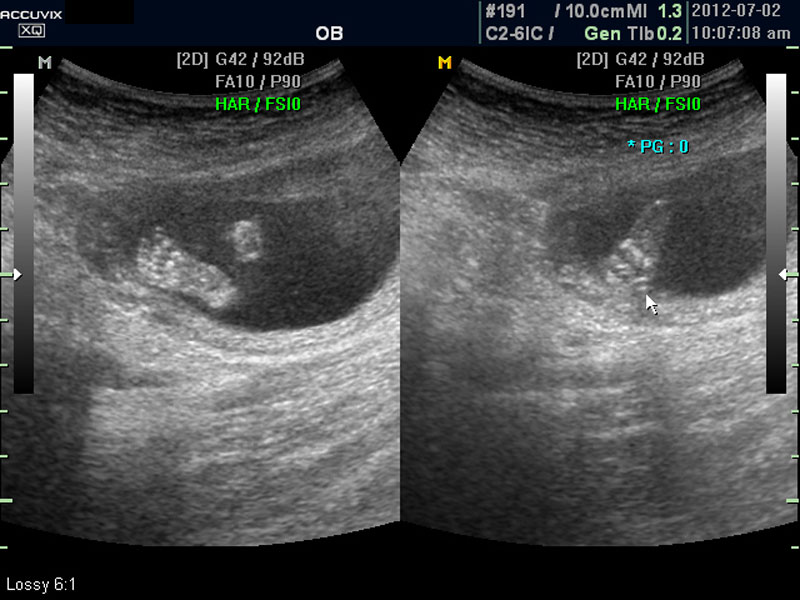

태아의 머리가 정상 모양인가 크기는 정상인가 하는 것을 살펴 본 후에는 태아의 크기를 측정하고 가슴, 복부, 엉덩이 부분, 상하지 부분이 정상인가 하는 것을 살펴 봅니다.

위 사진은 태아의 발바닥 사진인데 사진에서 보는 것처럼 그러나 이 시기는 손가락이나 발가락 또는  심장 내부의 구성 이상 등의 세세한 부분은 아직 크기가 작아서 제대로 확인하기 어려운 시기입니다.

따라서 부분 부분 살펴 보면서 해당 모습을 찍어서 저장하거나 인쇄하여 드리기도 하는 것이며 아래 사진은 태아의 다리 부분을 찍은 것입니다.